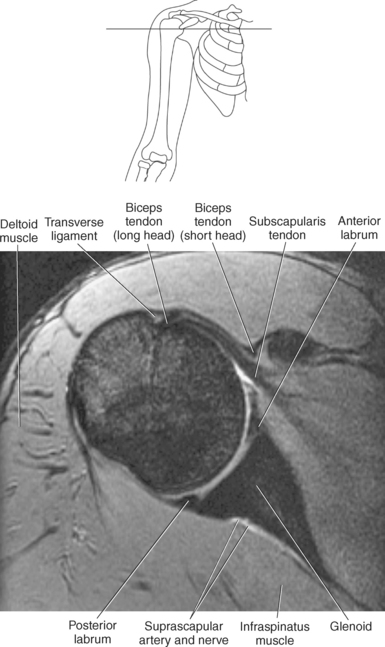

The edge of the glenoid fossa is surrounded by a fibrocartilaginous ring termed the glenoid labrum (glenoid lip) (Figure 9.17). The glenoid labrum is a fold of the articular capsule, which functions to deepen the articular surface of the glenoid fossa. Superiorly, the labrum blends with the long head of the biceps brachii muscle. In cross section it appears triangular (Figure 9.18). The three glenohumeral ligaments (superior middle, and inferior) are thickenings of the fibrous capsule that surrounds the shoulder joint; they contributes to the formation of the glenoid labrum (Figures 9.17 and 9.19). They extend from the supraglenoid tubercle of the scapula to the lesser tubercle of the humerus. Also aiding in strengthening the fibrous capsule is the coracohumeral ligament that passes from the lateral side of the coracoid process of the scapula to the anatomic neck of the humerus (Figure 9.19). The coracoacromial ligament is another important ligament located on the anterior portion of the shoulder. As this ligament joins the coracoid process and acromion, it forms a strong bridge, termed the coracoacromial arch, which protects the humeral head and rotator cuff tendons from direct trauma and prevents displacement of the humeral head superiorly (Figures 9.17 and 9.19). The coracoclavicular ligaments help to maintain the position of the clavicle, in relation to the acromion, by spanning the distance between the clavicle and coracoid process of the scapula (Figure 9.19). The acromioclavicular ligament, at the acromioclavicular joint, provides support for the superior surface of the shoulder (Figures 9.17 and 9.19). The transverse humeral ligament is a broad band of connective tissue passing from the greater tubercle to the lesser tubercle of the humerus, forming a bridge over the intertubercular groove for protection of the long head of the biceps tendon (Figure 9.19). The ligaments of the shoulder are demonstrated in Figures 9.20 through 9.30.

Figure 9.27 Axial, T1-weighted MR scan of shoulder.

Key: c, Clavicle; cc, coracoclavicular ligament; CP, coracoid process; ch, coracohumeral ligament; D, deltoid muscle; H, humeral head; SB, subscapularis muscle; SS, supraspinatus muscle; G, glenoid fossa; L, labrum; ss, supraspinatus tendon; b, tendon of long head of biceps muscle; IG, inferior glenohumeral ligament; mg, middle glenohumeral ligament; sb, subscapularis tendon; T, teres minor muscle.

Muscles of the scapula are described in Table 9.2 and demonstrated in Figures 9.34 through 9.52. The large deltoid muscle originates on the clavicle, acromion, and scapular spine to blanket the shoulder joint as it extends to insert on the deltoid tuberosity of the humerus. This powerful muscle forms the rounded contour of the shoulder and functions primarily to abduct the arm (Figure 9.48). The teres major muscle is a flat rectangular muscle that adducts and medially rotates the arm. It extends from the inferior angle of the scapula to the medial aspect or lip of the intertubercular groove of the humerus (Figure 9.49, A). The four remaining muscles, supraspinatus, infraspinatus, teres minor, and subscapularis, closely surround the scapula and compose the rotator cuff (Figures 9.49 through 9.52). The rotator cuff provides dynamic stability to the shoulder joint and allows for adduction, abduction, and rotation of the humerus. The supraspinatus, infraspinatus, and teres minor muscles are located on the posterior aspect of the scapula. The tendons of these muscles insert on the greater tubercle of the humerus. The supraspinatus muscle lies in the supraspinous fossa of the scapula and helps to abduct the arm. The tendon of the supraspinatus muscle is the most frequently injured tendon of the rotator cuff because of possible impingement as it extends under the acromioclavicular joint and continues over the humeral head (Figure 9.49, B). The infraspinatus muscle is a triangular muscle that lies below the scapular spine in the infraspinous fossa. It acts to laterally rotate the arm (Figure 9.49, A). Lying along the inferior border of the infraspinatus muscle is the elongated teres minor muscle, which also acts to laterally rotate the arm (Figure 9.49, B). The subscapularis muscle is the only muscle of the rotator cuff located on the anterior surface of the scapula; its tendon inserts on the lesser tubercle of the humerus (Figures 9.50 through 9.52). The subscapularis muscle acts to medially rotate the humerus. See sequential images through the shoulder (Figures 9.34 through 9.47).

The biceps brachii muscle is located on the anterior surface of the humerus and acts as a strong flexor of the forearm. The biceps brachii muscle is so named “biceps” because of its two expanded heads of proximal attachment (long and short). The tendon of the long head arises from the supraglenoid tubercle and courses through the intertubercular (bicipital) groove to merge with the tendon from the short head. The short head of the biceps brachii muscle originates from the coracoid process and joins with the long head to create the biceps brachii muscle, which terminates in two tendons. The stronger tendon inserts on the radial tuberosity, and the other tendon creates the bicipital aponeurosis, which radiates into the fascia of the forearm (Figure 9.55).